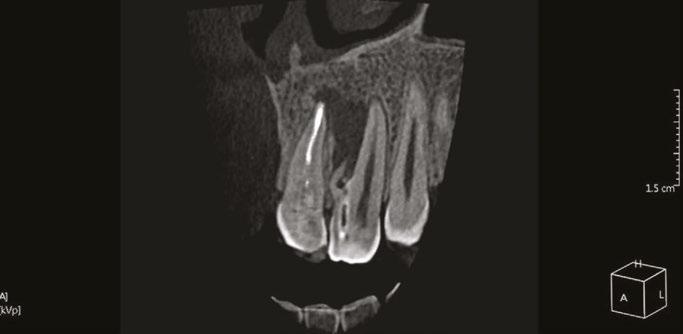

Dens invaginatus is a rare developmental malformation of the tooth that mainly affects the permanent maxillary lateral incisors. Endodontic treatment might be challenging due to the complex canal anatomy of the tooth with the diagnosed invagination. This invagination is often not connected to the main canal, so if it becomes infected, the main canal is usually unaffected. CBCT imaging is necessary to evaluate the complex anatomy and accurately determine the source of the periapical lesion and, thereafter, the treatment plan. The purpose of this article is to describe the careful evaluation of the source of infection by combining data from clinical findings and the use of 3D imaging. The correct obturation material should be selected, and the biomechanical preparation should be adjusted to the complex anatomic irregularities to ensure success.

order to visualize the complex anatomy, the use of a CBCT is an essential step. It is especially important to evaluate if there are any separate apical

foramina and communications between the main canal and the invagination.”

Cone beam computed tomography (CBCT) provides a three-dimensional (3D) representation of the tooth.8.9 It enables not only the understanding of the involvement of the main canal in the infection but also whether the invagination is completely separated from the main canal and may allow treatment of the DI without involvement of the main canal.8

Considering the irregular anatomy of the tooth, the patient was referred for a CBCT scan.

The CBCT scan confirmed the presence of a Type IIIa invagination and a large radiolucent lesion that was associated with the invagination in the lateral incisor and extended mesially towards the apex of the central incisor. Since the apex of the main canal in the lateral incisor was not involved, it was decided to limit the treatment to the invagination. The diagnosis of the periapex of the previously treated central incisor was unclear; there was either periapical healing or asymptomatic apical periodontitis; therefore, no intervention was done, and the tooth was kept for follow-up.

Figure 1: CBCT scan of the tooth demonstrating the radiolucent lesion surrounding the DI and extending to the apex of the central incisor Figures 2A-2D: 2A. Periapical radiograph of the dens. 2B. Hedstrom file in the invagination. 2C. The obturated enamel lining of the invagination with BC putty. 2D. Healing of the periapical lesion in the 1-year follow-up

In order to visualize the complex anatomy, the use of a CBCT is an essential step.8,9 It is especially important to evaluate if there are any separate apical foramina and communications between

the main canal and the invagination.8 This data should be evaluated in conjunction with clinical signs like swelling, sinus tract location and response to thermal tests.11 The use of high magnification and proper lighting is mandatory during access cavity preparation, negotiation of complex canal anatomy, and, if needed, during endodontic microsurgery.12 The use of a guided splint was also reported for the conservative pulp access during endodontic treatment of dens invaginatus.13